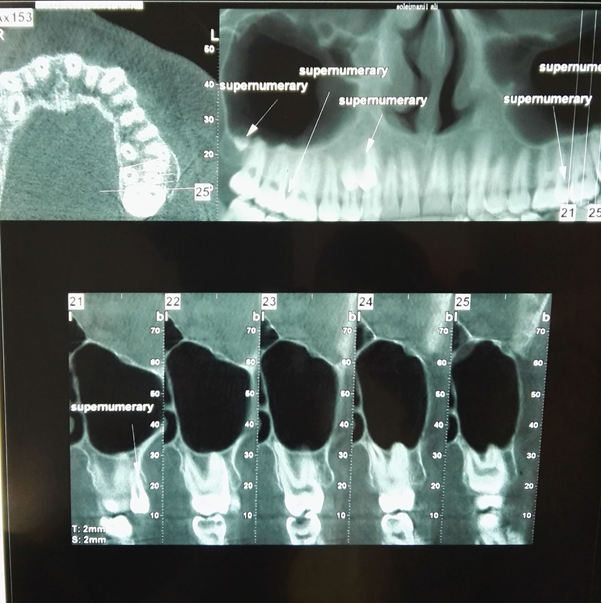

A 19-year-old Iranian male presented for an initial dental examination which involved taking panoramic radiograph. The patient had no complaint of pain, no sign of infection and was in good general health, with no other alterations. The patient has the history of bilateral ulnar polydactyly that was removed operatively at his early childhood. This bilateral ulnar polydactyly was not associated with syndactyly and polydactyly of the feet. On intraoral examination there were no abnormalities in the shape or size of the teeth or the relationship between the patient’s dental and chronological age. And also, there was no any other specific oral finding and relevant familial history of dental abnormalities. On clinical examination no craniofacial and skeletal anomaly related to supernumeraries (e.g. craniosynostosis, absence of clavicles, hypertelorism, ear deformity, etc.) was detected. The panoramic radiograph showed the presence of ten supernumerary teeth in all four quadrants (Fig. 1). On clinical examination it was found that all the permanent teeth including the third molars had erupted and the tooth number 36 had been extracted. CBCT (cone beam computed tomography) of the mandible and maxilla was taken to confirm the location of the supernumerary teeth and impact of these teeth on the adjacent teeth (Fig. 2, 3).

Fig1. The panoramic radiograph showed the presence of ten supernumerary teeth in all four quadrants

Fig2. Axial, cropped reconstructed panoramic and cross sectional CBCT views of the maxilla

The first quadrant showed the presence of three supernumerary teeth. One of them was a distomolar (fourth molar), exhibiting a microdent tooth without complete root formation which lied in the right maxillary tuberosity at the apical region of the 18. A supernumerary premolar had buccally erupted between the 16 and 17. This tooth was normal in size and morphology as a premolar. Another supernumerary premolar was also found palatally to and at about the middle premolar as well. It seems that this supernumerary tooth had resorbed the palatal root of the 14. The gingiva around these teeth appeared healthy, with periodontal probing depths of 2 mm and no bleeding. There were also two supernumerary molars in second quadrant at the level of apical third of the roots of the 28. Both of these exhibit microdontia without complete root formation. These two supernumerary teeth seem to have close proximity with each other. One erupted supernumerary tooth was found in the second quadrant, buccal to and between the 26 and 27. These teeth had fully formed crown and root with normal morphology and size of a premolar. In the left mandibular premolar region there were three supernumerary teeth, all with fully formed crowns and roots. Two of these were unerupted and similar to normal premolars in size and morphology. One of them was between 35 and 36 lingually that resorbed lingual region of the root of 35 and  mesial root of 36 at the middle third of it. The other was between 34 and 35 lingually and resorbed lingual part of the 34 and 35 in their root region too. Another erupted supernumerary tooth which found between 33 and 34 buccally exhibited the normal morphology and size as a canine. One supernumerary tooth was found in the right mandibular quadrant in the premolar region between 45 and 46. This erupted tooth had fully formed crown and root, and  resembled the size and morphology of a normal premolar as well.